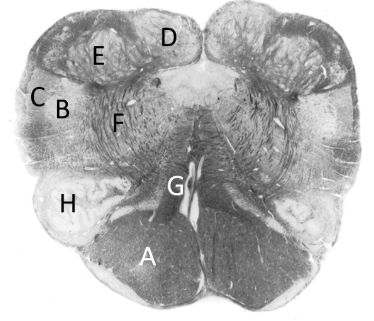

at what level is this?

mid pons

what is a?

cerebellum

what is b?

superior cerebellar peduncle

what is c?

middle cerebellar peduncle

what is d?

trigeminal nerve

what is e?

pyramidal fibres

what is f?

transverse pontine fibres

what is g?

4th ventricle

what is h?

median longitudinal fasciculus (p)

what is j?

medial lemniscus (p)

what is k?

spinothalamic tract (p)